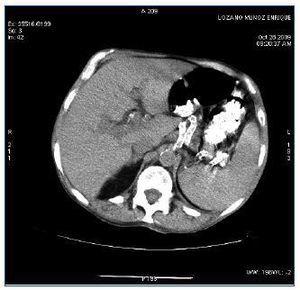

Se describe el caso de un paciente de 67 años de edad en programa de hemodiálisis con los antecedentes personales de hipertensión arterial, serologías positivas de virus de hepatitis C, enfermedad renal crónica por nefroangiosclerosis, que inicia hemodiálisis en 1989, trasplante renal en 1990, diabetes mellitus postrasplante; reinicia diálisis en septiembre de 2007. En tratamiento desde hacía 3 meses con dosis de 30 mg/día de prednisona ante la sospecha clínica inicial de una intolerancia al injerto renal. Ingresa por fiebre vespertina con sudoración sin foco aparente de una semana de evolución. La anamnesis y la exploración física eran inespecíficas, mostrando únicamente astenia y pérdida de peso en los últimos meses. Se obtienen cultivos de sangre, orina, líquido pleural y esputos que resultan negativos, así como estudios radiológicos de tórax y abdomen. Se comienza antibioticoterapia de amplio espectro y se continúa el estudio para buscar el foco causante de la fiebre. Se realizan ecocardiogramas transtorácico y transesofágico que resultan normales. En únicamente uno de los hemocultivos seriados posteriores se aísla Staplylococcus aureus, por lo que se modifica el tratamiento antibiótico y se realizan de nuevo ecocardiogramas transtorácico y transesofágico que descartan la existencia de una endocarditis. Ante la persistencia de la fiebre se añade tratamiento antifúngico. En la analítica destaca PCR 13 U, proteínas totales 5,1 g/dl, albúmina 2,3 g/dl, leucocitos 3.600 (80% neutrófilos), Hgb 12,4, hematocrito 37%, plaquetas 102.000 x 109. La ecografía abdominal muestra una esplenomegalia con múltiples y pequeñas imágenes hipoecogénicas bien definidas, de hasta 1 cm de diámetro que podrían corresponder a microabscesos esplénicos múltiples. Se realiza TAC toracoabdominal que muestra en el tórax la existencia de múltiples adenomegalias mediastínicas, evidentes en espacio retrocavo-pretraqueal, paraaórtico, paratraqueal derecho superior e inferior y subcarinal, de hasta 2 cm de diámetro. Derrame pleural bilateral y pericárdico. Parénquima pulmonar con patrón «en mosaico». Se aprecian al menos tres imágenes focales, seudonodulares, de alrededor de 1 cm de diámetro, en situación periférica, subpleural, una en segmento anterior del lóbulo del lóbulo superior derecho y dos en lóbulo superior izquierdo. Infiltrados irregulares intersticioacinares en ambas bases en abdomen y pelvis, esplenomegalia, con múltiples imágenes focales hipodensas, de contornos no bien definidos, menores de 1 cm, compatibles con microabscesos esplénicos y al menos dos pequeñas imágenes hipodensas puntiformes en el hígado (figura 1). Planteamos el diagnóstico diferencial con un carcinoma microcítico de pulmón o con un linfoma. Se realiza biopsia de médula ósea que muestra una hipoplasia de células medulares sin evidencia de células neoplásicas. La gammagrafía con galio-67 no muestra focos de actividad inflamatoria/infecciosa. En PET/TAC se aprecian adenopatías hipermetabólicas en la encrucijada cérvico-supraclaviculares, axilares y mediastínicas, nódulos pulmonares hipermetabólicos subpleurales múltiples. Esplenomegalia con múltiples nódulos hipermetabólicos, imágenes focales hipermetabólicos en cuerpos vertebrales de C3, C4, D8 y cuarto arco costal. Pese al tratamiento antibiótico de amplio espectro y antifúngicos el paciente continúa con picos febriles con importante síndrome constitucional y caquectización. Todos los cultivos, serologías, así como el test de PPD intradérmico, cultivos de BK en esputo, líquido pleural y orina y adenosindesamina en líquido pleural son repetidamente negativos. Se realiza mediastinoscopia con biopsia de dos de las adenopatías. La anatomía patológica es descrita como una linfadenitis granulomatosa necrosante extremadamente indicativa de infección por micobacterias; con las técnicas histoquímicas para microorganismos no se identifican bacilos ácido-alcohol resistentes ni hongos. Ante este hallazgo y la clínica del paciente, con una alta sospecha de infección tuberculosa decidimos iniciar tratamiento con tuberculostáticos (rifampicina, isoniazida y etambutol).

Figura 1. TAC con contraste a nivel esplénico con múltiples lesiones.